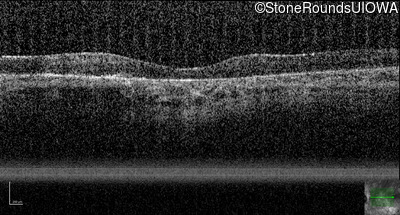

Age at visit: 38 years

This 38 year old woman had normal vision until age 22 when she noticed poor night vision when working as a camp counselor after college. Her hearing loss was first noticed at age 3 and was correctable with hearing aids.